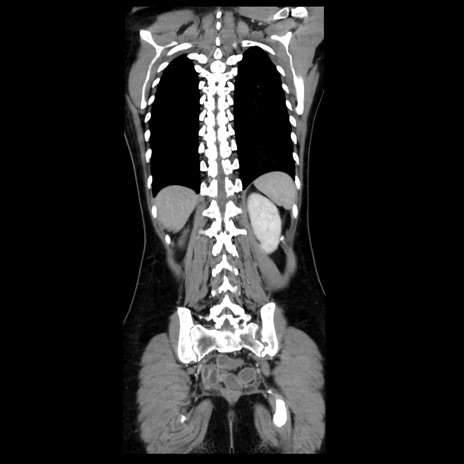

症例39(冠状断像)

【症例】40歳代女性

【主訴】上下腹部痛

【現病歴】2日目から下腹部痛あり。夜間は痛みで眠れなかった。昨日より上腹部痛と下痢が出現。臥位で痛みは軽快したため、休んでいた。本日になって臥位でも立位でも痛みが強くなってきたため救急要請。

【既往歴】子宮内膜症

【身体所見】部:平坦・軟、左上下腹部に圧痛あり、反跳痛あり。

【データ】WBC 21800、CRP 26.78

CT